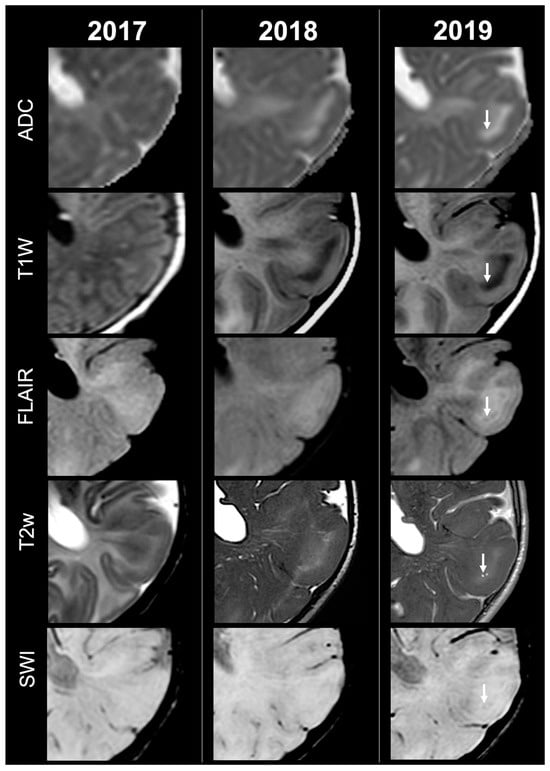

Cortical Tubers’ Transformation in Pediatric Patients Diagnosed with Tuberous Sclerosis Complex: A Retrospective Longitudinal MRI Analysis

Background: Cortical tubers (CTs) are hallmark brain lesions in tuberous sclerosis complex (TSC), historically considered stable in number over time; prior literature has correlated overall CT burden on magnetic resonance imaging (MRI) with disease severity. As longitudinal imaging studies assessing CTs’ evolution over time are lacking, we aim to investigate temporal changes in CTs—both in number and signal—on MRI in a cohort of pediatric TSC patients. Methods: A retrospective single-center analysis was conducted on 57 pediatric TSC patients who underwent longitudinal MRI studies in a 10-year span. Required MRI sequences included volumetric unenhanced T1-weighted, SWI, T2w and/or FLAIR. CTs were evaluated by two neuroradiologists and classified into five subtypes (A, B, C1, C2, D) according to signal characteristics. Statistical comparison was performed using t-tests. Results: Paired t-test analysis demonstrated a significant longitudinal increase in the overall number of CTs, rising from 16.11 ± 12.43 at baseline to 18.77 ± 13.29 at follow-up (mean difference = −2.67, 95% CI [−3.94, −1.39]; t (56) = 4.19; p < 0.0001), corresponding to a moderate effect size (Cohen’s d ≈ 0.56). When stratified by age, patients <2 years—representing the incompletely myelinated subgroup—showed a more pronounced increase in CT burden, from 19.46 ± 15.21 to 24.17 ± 15.75 (mean difference = −4.71, 95% CI [−7.37, −2.04]; t (23) = 3.65; p = 0.0013; d ≈ 0.75). In contrast, patients aged ≥2 years demonstrated a smaller but still significant increase, from 13.67 ± 9.45 to 14.85 ± 9.64 (mean difference = −1.18, 95% CI [−2.08, −0.28]; t (32) = 2.68; p = 0.0115; d ≈ 0.46). Direct comparison between the two subgroups using Welch’s two-sample t-test confirmed that the mean CT count in patients <2 years was significantly higher than in those ≥2 years (mean difference = 3.53 ± 1.36; t = 2.59; df = 28.4; p = 0.0075), with a large effect size (Cohen’s d ≈ 0.78). Type C1-C2 tubers evolved from pre-existing earlier-stage lesions, while most newly visible CTs over time were type A-B. Type D tubers remained rare and derived from earlier-stage CTs. Conclusions: Contrary to previous assumptions, CTs in pediatric TSC showed a tendency to increase in number and evolve in signal over time, thus challenging the notion of stability and suggesting dynamic behavior. Incomplete myelination in early infancy may impact MRI CTs detection by reducing contrast with surrounding brain tissue, potentially leading to their underestimation/misidentification. Full article

Show Figures

Figure 1